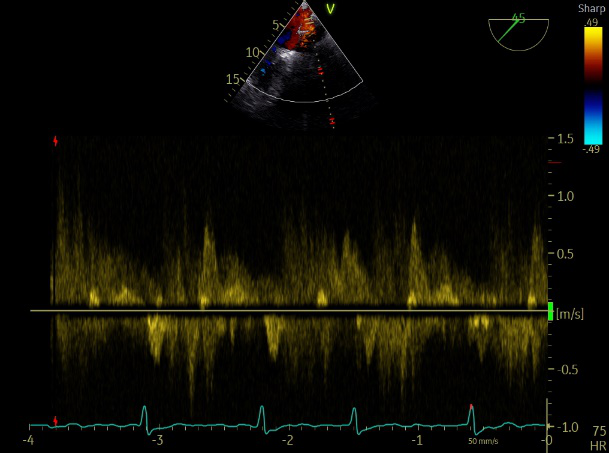

肺静脉血流频谱呈收缩期反向

患者麻醉方式为全麻,建立静脉通路后,穿刺右侧股静脉,预埋ProGlide缝合器,食道超声指导下房间隔穿刺成功,将Superstiff导丝送至左房,应用18F鞘管扩张穿刺部位,沿导丝将导引导管送入左房,MitraClip调整后顺利到达二尖瓣目标位置,在X线及食道超声辅助下,将Mitraclip NTR成形夹精确定位后,成功夹合二尖瓣A2-P2区,超声显示反流明显减少,多切面证实夹合组织充分,肺静脉多普勒波形由反向恢复正常,手术顺利结束,安返普通病房。